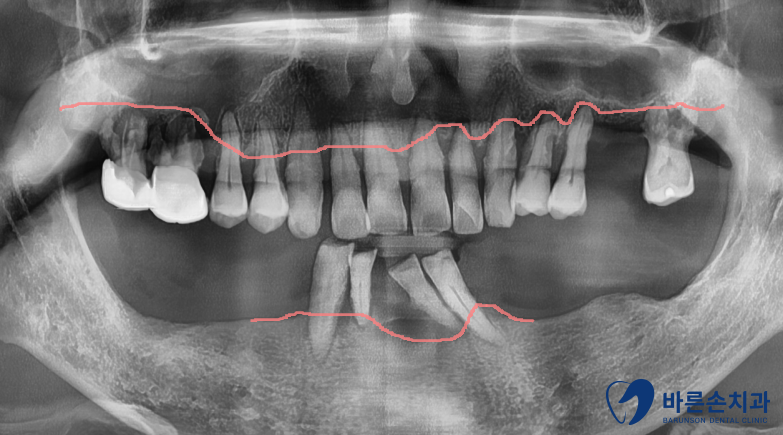

초진 사진

치아를 보시면 주변에 치태, 치석이 방치가 되어있습니다.

잇몸도 빨갛게 부어있고 치아도 옆으로 쓰러져있네요.

당연히 식사 시 매우 불편하십니다 ㅠㅠ